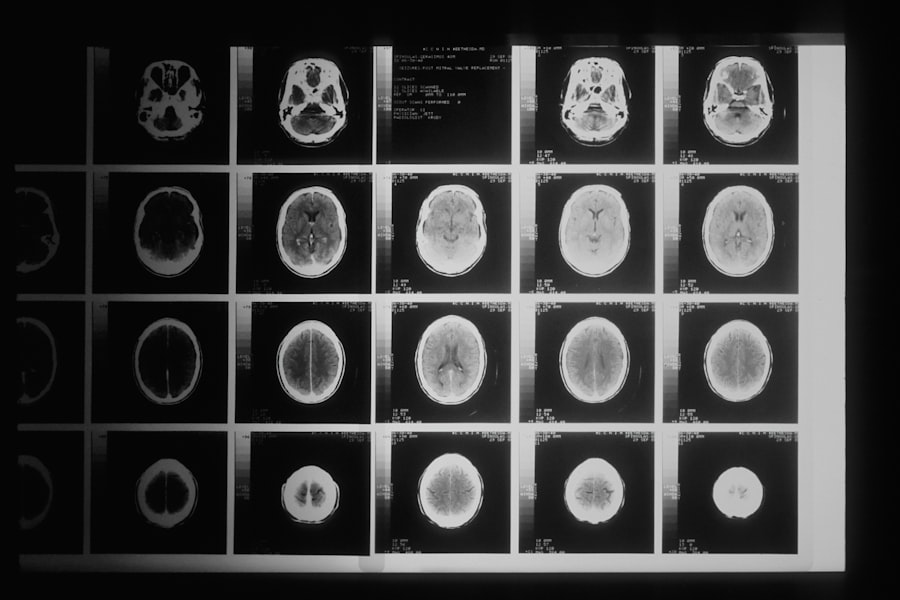

Accurate diagnosis of neuroparasitic infections is vital for effective treatment and management. As you explore diagnostic techniques in neuroparasitology, you will encounter various methods used to identify these infections in clinical settings. Traditional approaches often involve serological tests to detect antibodies against specific parasites or imaging techniques like MRI or CT scans to visualize lesions caused by infections.

In recent years, advancements in molecular techniques have revolutionized diagnostic capabilities. Polymerase chain reaction (PCR) assays allow for rapid detection of parasitic DNA in cerebrospinal fluid or tissue samples, providing a more precise diagnosis than traditional methods. As you delve deeper into these techniques, you will appreciate how they enhance our understanding of neuroparasitic infections and facilitate timely interventions.